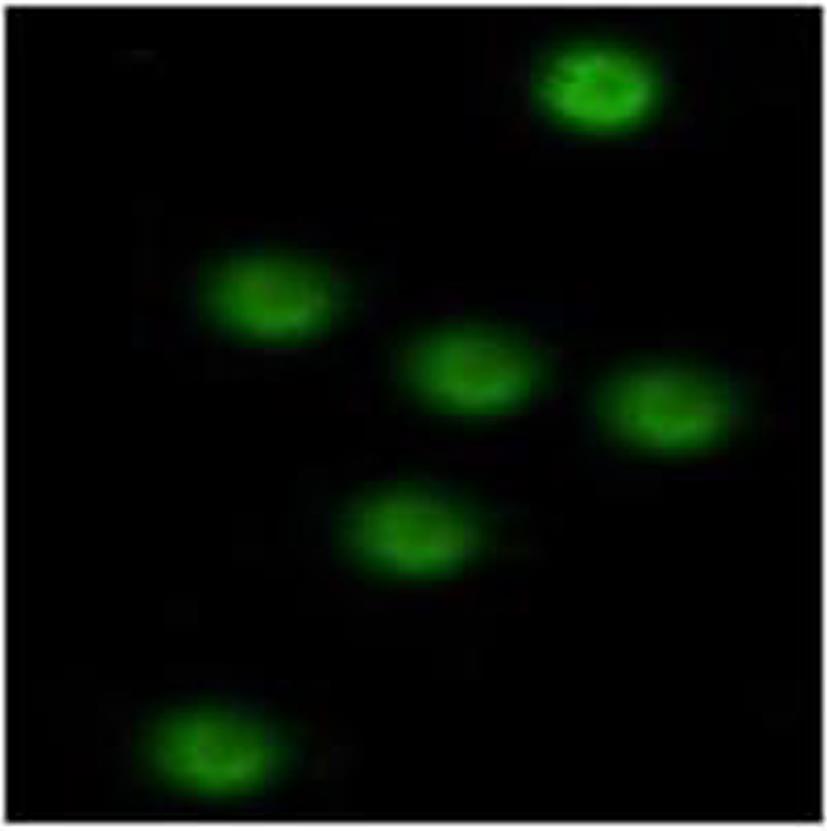

Preliminary identification of the cloning, expression, and function of Marmota himalayana type I interferon receptor β subunit

Ying TAO, Dongliang YANG, Baoju WANG, Yi LIU, Wenjia GUI, Zhi LI, Hebin FAN

2024, 40(2): 278-283. DOI: 10.12449/JCH240210

Abstract(846) HTML (320) PDF (920KB)(60)

Abstract:

Objective  To clone the gene of Marmota himalayana type ‍Ⅰ interferon receptor β subunit (mhIFNAR2), and to perform antibody preparation and functional identification.  Methods  RT-PCR was used for amplification in the spleen tissue of Marmota himalayana to obtain the sequence, which was cloned to the prokaryotic expression vector pRSET-B to express the recombinant protein. Electrophoresis and Western blot were used for identification. BALB/c mice were immunized with the recombinant protein to prepare the polyclonal antibody of its extracellular domain; immunohistochemistry, immunofluorescence assay, and Western Blot were used for identification, and the method of siRNA blockade was used to investigate its function. An analysis of variance was used for comparison of continuous data between multiple groups, and the least significant difference t-test was used for comparison between two groups.  Results  A fragment of mhIFNAR2 (149‍ ‍—‍ ‍1 ‍300 bp) was obtained from spleen tissue, which showed the highest homology of 98.05% in marmot. A prokaryotic expression plasmid was successfully constructed for expression of the extracellular domain of the mhIFNAR2(50-181aa) and was named pRSET-B.mhIFNAR2, and the recombinant protein expressed by this plasmid had a molecular weight of 27 kD, a purity of about 95% after purification, and a concentration of 160 μg/mL. After BALB/c mice were immunized with the purified recombinant protein, 1∶1 000 specific polyclonal antibodies were obtained, and immunohistochemistry and immunofluorescence assay showed the expression in cell membrane and cytoplasm. Among the three siRNAs synthesized, the siRNA starting from the 277 locus (siRNA277) could silence the expression of target genes and weaken the interferon signaling pathway compared with the blank control group and the negative control group (both P<0.05).  Conclusion  The fragment of mhIFNAR2 is obtained, and the polyclonal antibody for the extracellular domain of mhIFNAR2 is successfully prepared, with relatively high titer and specificity, and can be used for immunohistochemistry, immunofluorescence assay, and Western blot.